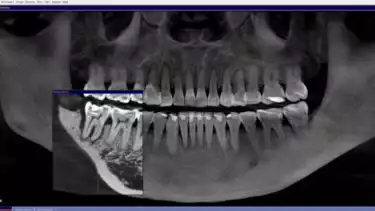

- Dok. Devya Dental Clinic

Setelah melihat hasil rontgen, drg. Devya menjelaskan, “Sebelah kanan kondisinya masih lebih baik, jadi itu yang akan kita prioritaskan dulu.” Tulang di sekitar gigi kanan Marcella masih cukup kuat untuk mendukung gigi, membuat kondisinya lebih stabil dibandingkan gigi kiri. Oleh karena itu, perawatan difokuskan terlebih dahulu pada gigi kanan untuk memaksimalkan peluang pemulihan sebelum beralih ke gigi lainnya.